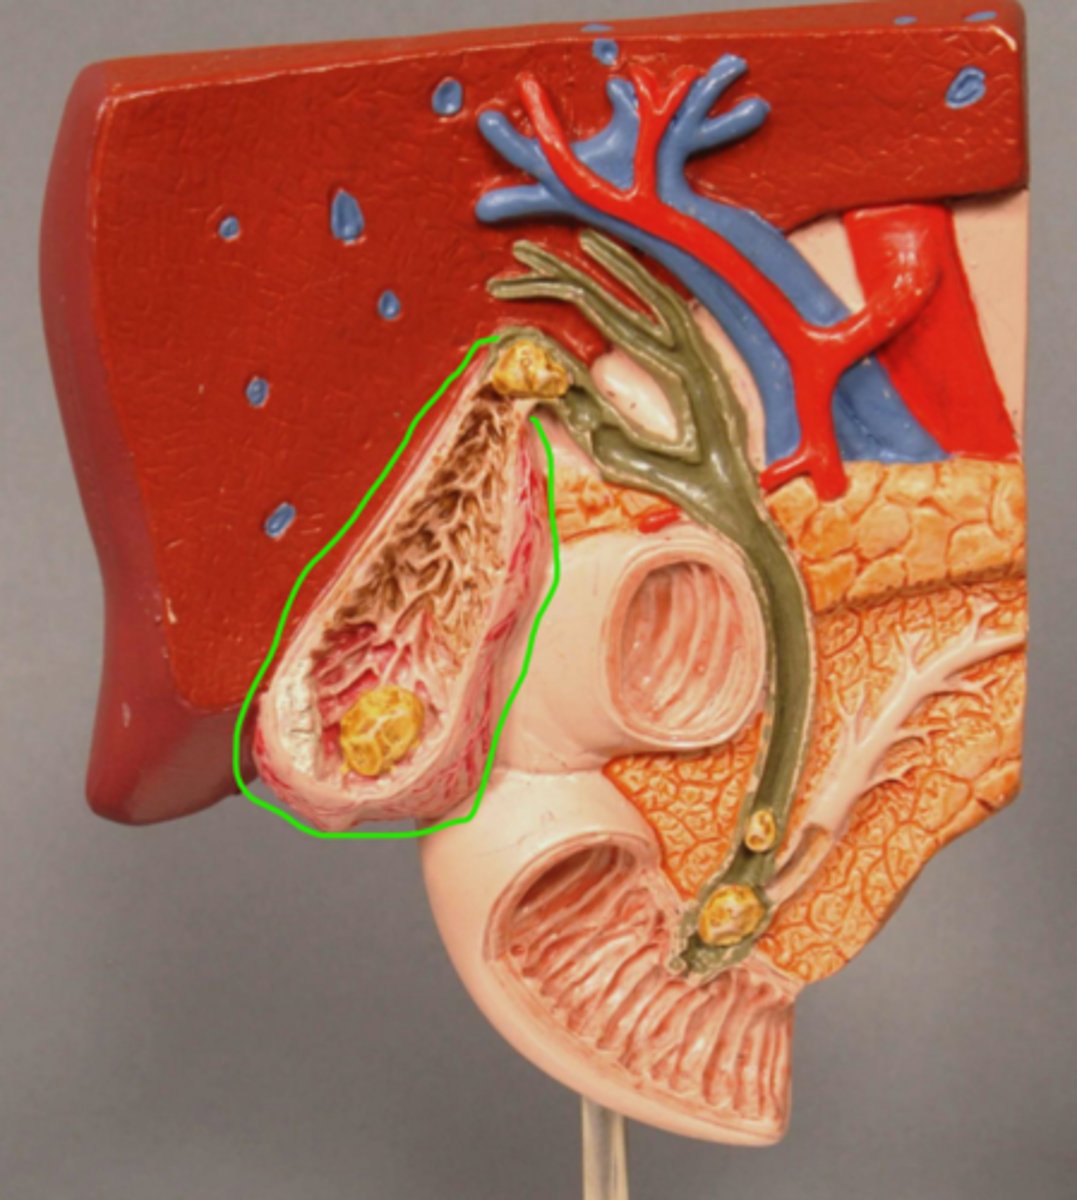

Gallbladder

Gallbladder Mucosa

Gallstone in Fundus of Gallbladder

Acute Inflammation of Gallbladder (Cholecystitis)

Scarred wall of Gallbladder (Following Chronic Inflammation)